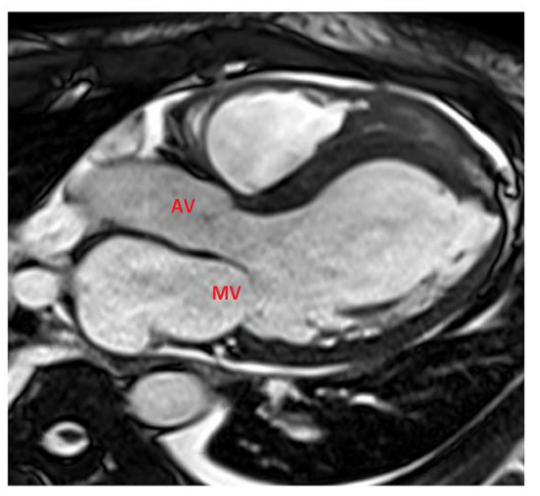

Figure 1E: 50-year-old male with history of T-ALL and febrile neutropenia. E, SSFP three-chamber cardiac MR view shows no evidence of valvular vegetations on the aortic or mitral valves. AV: Aortic valve, MV: Mitral valve.

A 50-year-old male with diagnosed T-cell acute lymphoblastic leukemia (T-ALL) on Hyper-CVAD (hyper-fractionated cyclophosphamide, vincristine, doxorubicin (Adriamycin), and dexamethasone) chemotherapy cycle 2, presented with fever, chills, and malaise. On admission, he was neutropenic (ANC <100/µL) and hemodynamically stable. Empiric broad-spectrum antibiotics were initiated for febrile neutropenia. Chest CT revealed a 1.2 cm cavitary nodule in the right upper lobe (Figure 1A) and ill-defined, lobulated hypoattenuating lesion measuring approximately 7×3 cm within the interventricular septum (Figure 1B), raising suspicion for fungal infection in the setting of profound neutropenia. During hospitalization, the patient developed a new-onset tremor. Brain MRI demonstrated a 3.4 cm mass in the left frontal lobe with surrounding vasogenic edema, showing ring-like enhancement on post-contrast sequences, consistent with a possible fungal abscess or metastatic septic embolus. Stereotactic brain biopsy pathology confirmed fungal infection (broad, aseptate hyphae morphologically compatible with Mucorales). Peripheral blood cfDNA testing identified Cunninghamella species (a member of the Mucorales), supporting the diagnosis of invasive cerebral mucormycosis (Cunninghamella). A PET/CT scan, conducted to assess disseminated fungal infection, identified a hypermetabolic fluid collection along the inferior wall of the heart, abnormal FDG uptake in all four cardiac chambers, and a small pericardial effusion (Figure 1C). These findings raised concerns for cardiac involvement, suggesting a possible myocardial abscess and associated inflammatory activity. Transthoracic echocardiogram reported anthracycline-induced cardiotoxicity with reduced ejection fraction EF: 35%, no vegetations visualized on the valves. A cardiac MRI (Siemens 1.5T) was performed using stacked shortaxis and four-chamber cine steady-state free precession (SSFP) sequences to assess morphology, function, and wall motion. Tissue characterization included pre- and post-contrast T1-weighted imaging, first-pass perfusion, and late gadolinium enhancement (10 minutes post-contrast) with phase-sensitive inversion recovery (PSIR), which provide improved nulling of normal myocardium and better delineation of abnormal tissue such as inflammation, necrosis, or abscess. Short-axis cine SSFP imaging demonstrated a 7×3 cm hyperintense intramyocardial lesion in the mid-toapical interventricular septum extending into the right ventricle (Figure 1D), with associated myocardial edema, regional hypokinesis, and reduced systolic function (LVEF: 30%). There was no evidence of infective endocarditis involving the native heart valves, with no valvular vegetations, abnormal thickening, or perivalvular extension identified (Figure 1E). First-pass perfusion revealed a non-enhancing, multilobulated lesion without viable microvasculature in the corresponding region (Figure 1F). Late gadolinium enhancement with PSIR demonstrated a septal intramyocardial mass with a central non-enhancing core consistent with abscess formation, surrounded by a rim of peripheral enhancement and mid-wall adjacent myocardial uptake, indicating associated inflammatory involvement (Figure 1G). The case was discussed at a multidisciplinary conference attended by specialists in radiology, cardiothoracic surgery, and interventional cardiology. Due to the lack of a safe surgical or percutaneous method to evacuate the intramyocardial abscess, the team decided to pursue nonoperative management. This approach involves targeted antifungal therapy and regular imaging surveillance to closely monitor the condition. A cardiac MRI conducted at a fourweek interval showed a reduction in the size of the interventricular myocardial abscess, which now measures 3.5x1.5 cm compared to its previous dimensions. Cine SSFP sequences indicated a decrease in perilesional edema, while post-contrast delayed enhancement imaging revealed a reduction in both the thickness and intensity of the surrounding rim (Figure 1H). Additionally, there was a slight improvement in left ventricular systolic function, with a left ventricular ejection fraction (LVEF) of 35% and no new regional wall motion abnormalities detected. It was recommended to continue antifungal therapy and perform imaging surveillance at short intervals. Despite interval radiologic improvement of the interventricular myocardial abscess, the patient subsequently developed superimposed Pseudomonas aeruginosa bacteremia complicated by septic shock and ultimately succumbed to multiorgan failure.